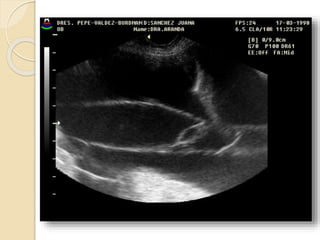

Teratomas

Los teratomas quísticos o tumores

dermoides contienen elementos de las tres

capas embrionarias y por lo tanto están

formado por distintos tejidos: hueso,

cartílago, pelo, sebo, tejido nervioso, etc.